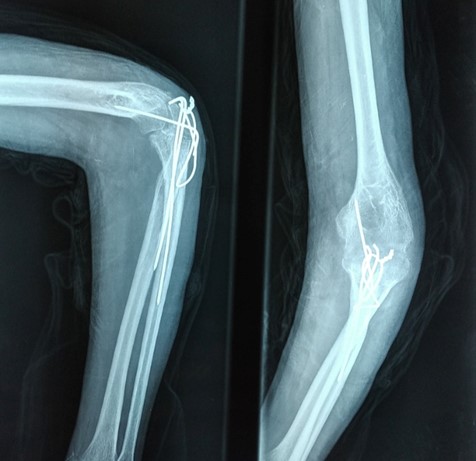

The patient was placed in a lateral recumbent position with the elbow placed on a support. A midline paratricipital posterior approach was used. The ulnar nerve was isolated, the elbow joint was approached from lateral and medial sides with triceps sparing. The olecranon fossa, radial head and trochlear notch contained fibrous tissues and osteophytes which were removed, arthrolysis was then performed. Reduction was obtained but the humeral trochlea could not be lodged perfectly into the trochlear notch. We proceeded to perform an enlarging osteoplasty of the trochlear notch by performing an osteotomy at the base of the olecranon. Two 1.8mm K wires were then passed through the olecranon and the two fragments were distracted by 2mm in order to enlarge the trochlear notch. We then passed a cerclage wire in a figure of 8 loop and filled the defect created by our osteotomy with some of the periarticular fragments we had earlier resected. The elbow joint was then perfectly reduced, peroperative mobilisation of the elbow joint showed a range of motion of 115°(Extension 15°,Flexion 130°). The ulnar nerve was then transposed anteriorly and the elbow joint was stabilised in 90° flexion by an olecrano-humeral K wire. The lateral collateral ligament which was found to have been sectioned was reattached by transosseous sutures, the medial collateral ligament was intact but retracted and was released in order to reduce the joint, we did not need to perform a triceps lengthening procedure in order to achieve reduction. The wound was then washed with saline solution and closed and a posterior above elbow slab was applied. At 3 weeks post operatively the slab and the K wire blocking the elbow joint were removed and the patient was advised to begin physiotherapy.(Figure 2)

Figure 2: Post operative X ray showing a congruent elbow joint